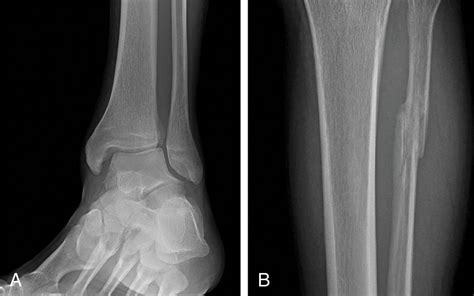

Diagnosis of Proximal Fibula Fracture

Diagnosing a Proximal Fibula Fracture involves a combination of physical examination and imaging tests. The diagnostic process typically includes:

• Physical examination: A healthcare provider will assess the injured area for pain, swelling, and deformity.

• X-rays: Imaging tests to visualize the bone and determine the location and severity of the fracture.

• CT scans or MRI: In some cases, more detailed imaging may be required to assess the extent of the injury and plan treatment.